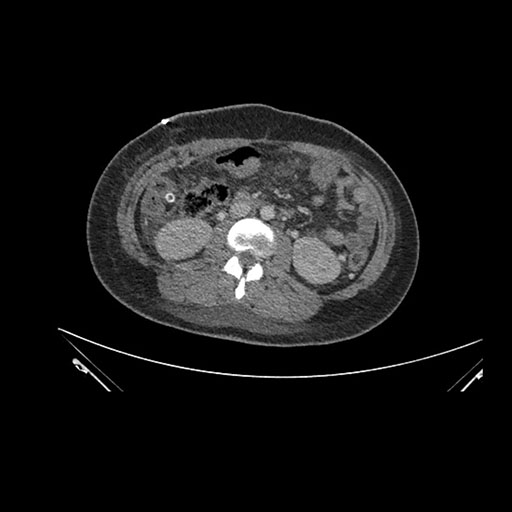

Imaging Analysis

Look through the patient's CT scan to identify any areas of concern for the necessary procedure.

Coronal Arterial

Based on initial findings, which issue(s) would you be most concerned about?